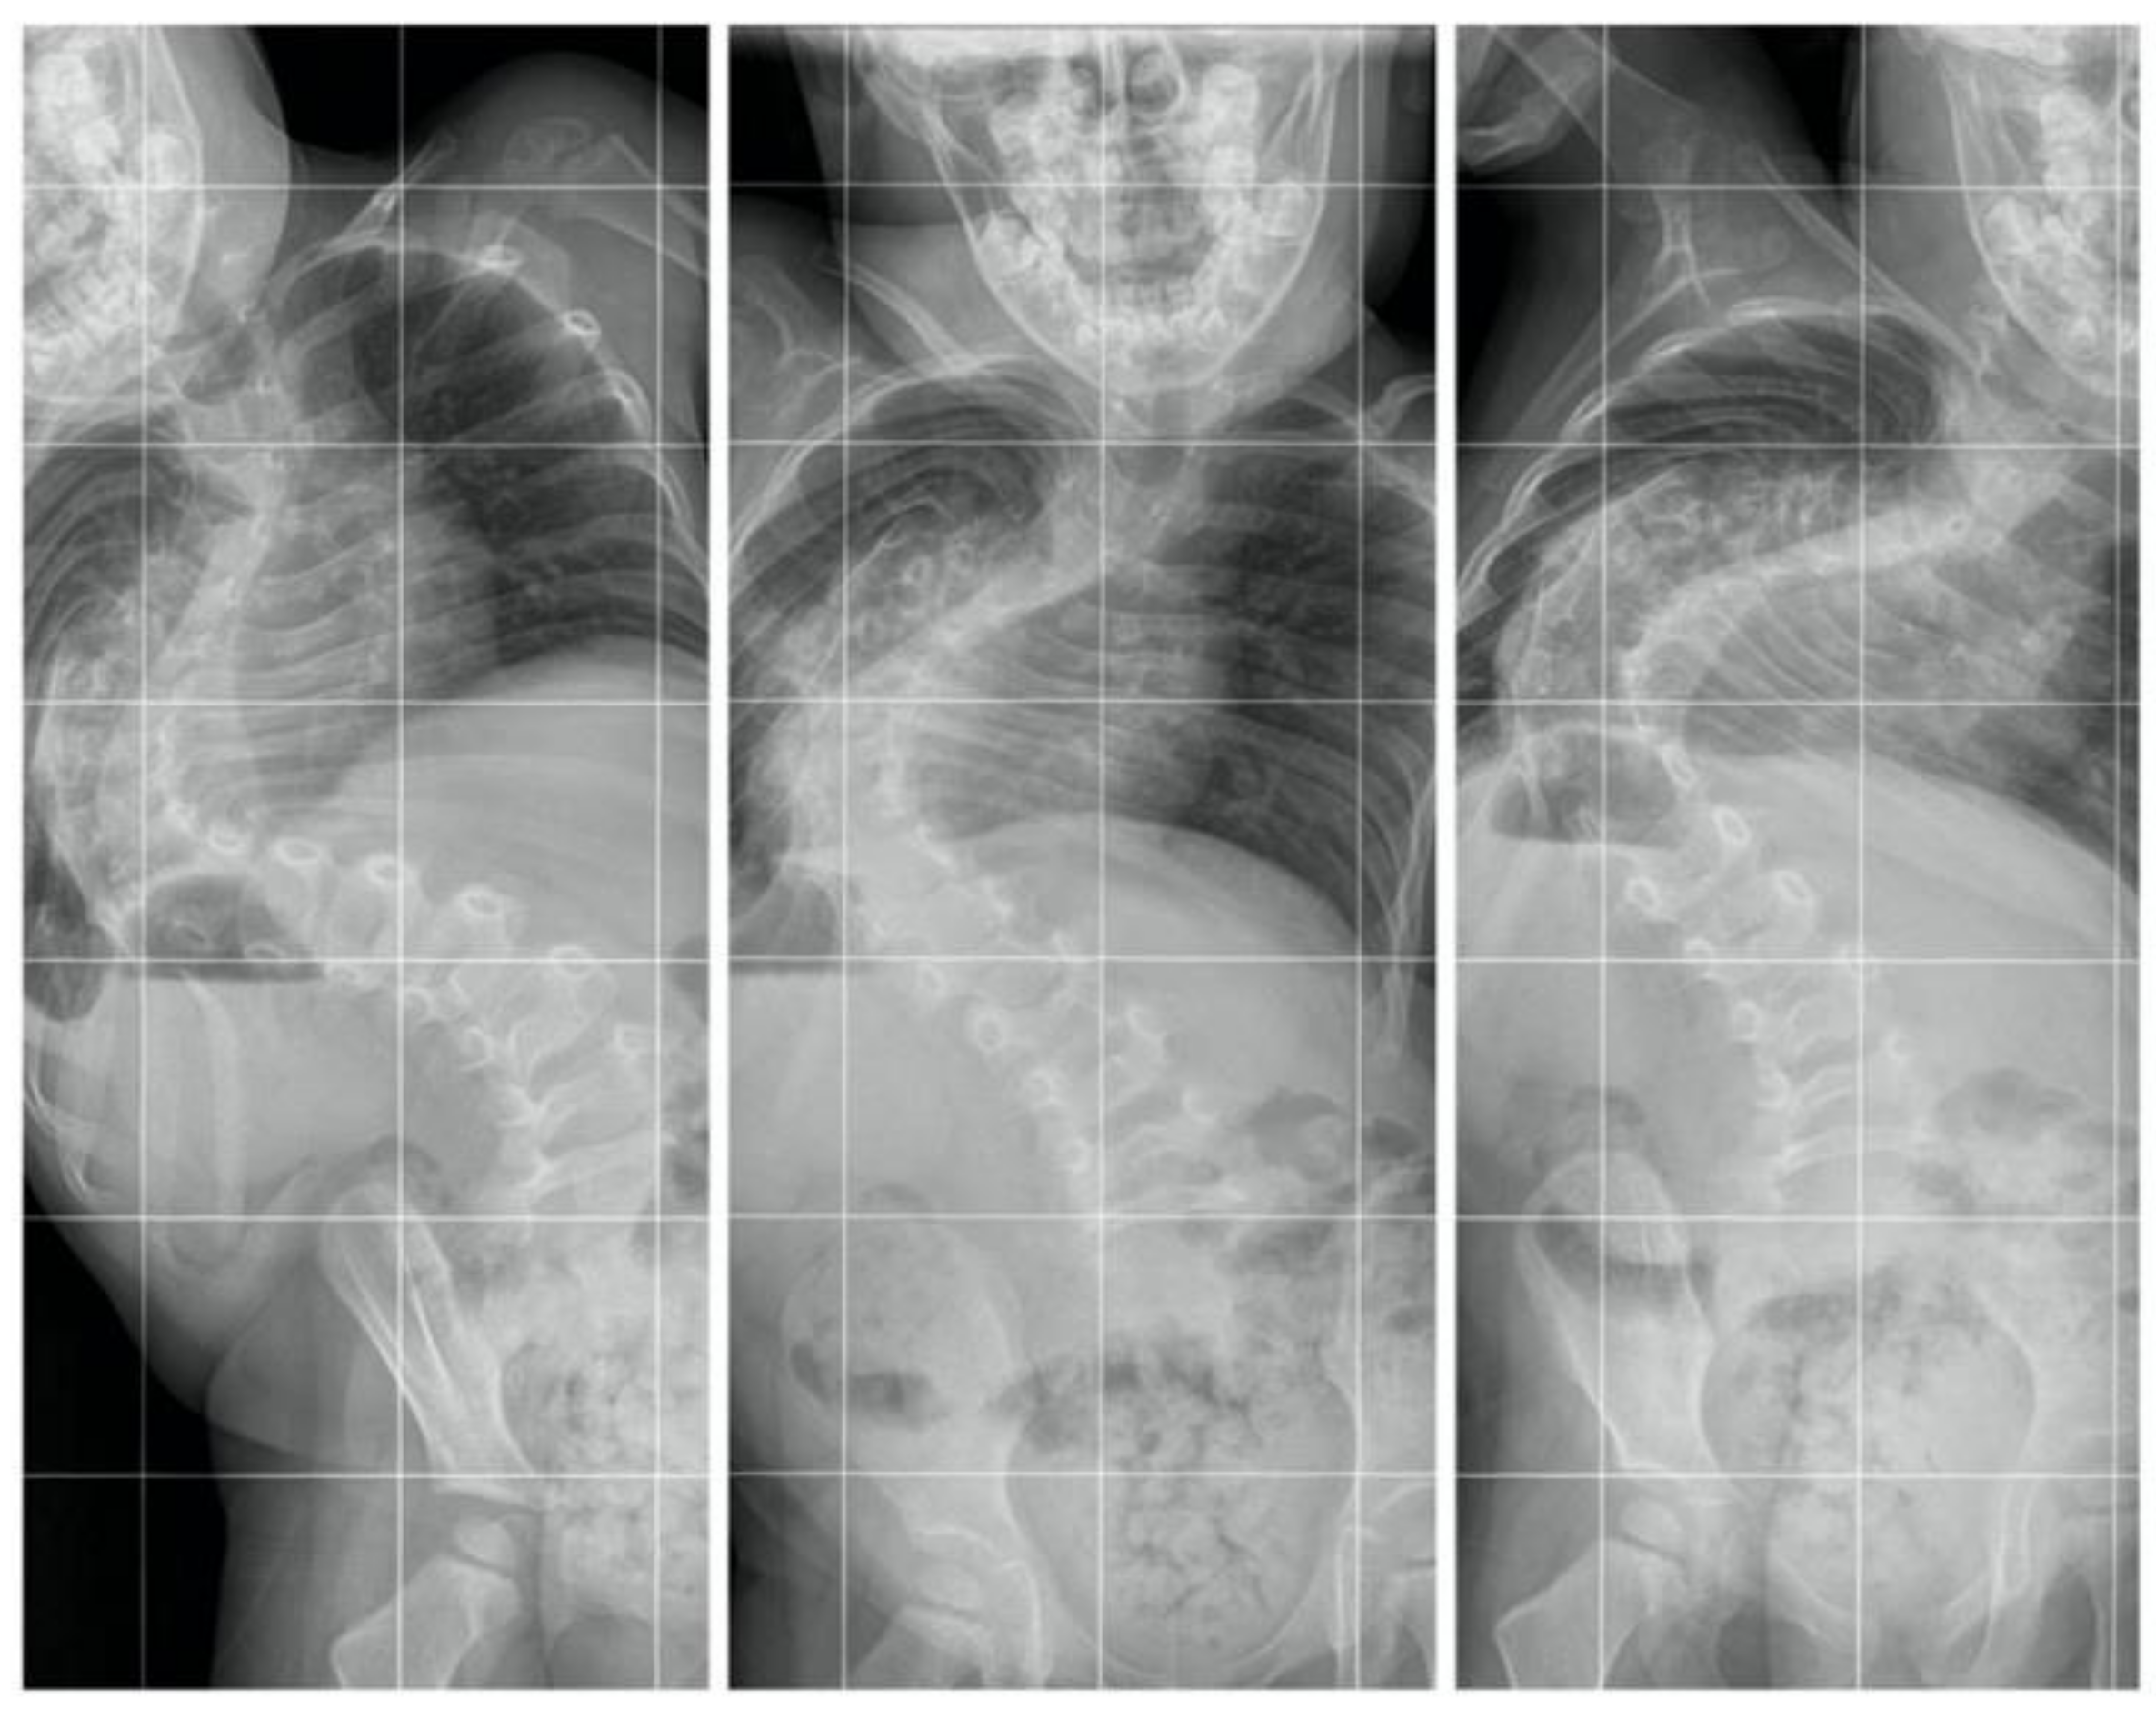

All examinations, specialist consultations, and clinical statuses showed other causes of spinal deformity. We diagnosed early-onset idiopathic scoliosis with fast progression, which qualified for surgical treatment with growing rods (Figure 3). The flexibility was approximately 30%, so we performed anterior release and spine correction with intraoperative halo traction (Figure 4).

Figure 3.

X-rays and clinical preoperative images.

Figure 4.

AP standing bending films.